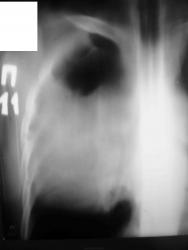

Мужчина 36 лет, рентгеногафия и КТ грудной полости.

Жалобы на субфебрильную температуру, боли в грудной клетке справа, слабость, похудание. ФГ 10 месяцев назад - норма.

Интенсивное, однородное затемнение в средних отделах справа, слева норма - мною был заподозрен м/долевой плеврит, пациент был направлен в областной центр торакальной хирургии. Затем онкодиспансер, затем институт рака в Киеве. Результат гистологии тератобластома средостения. 2 курса химиотерапии контрольное КТ в октябре - отрицательная динамика.

Р-графия от 30.11.09